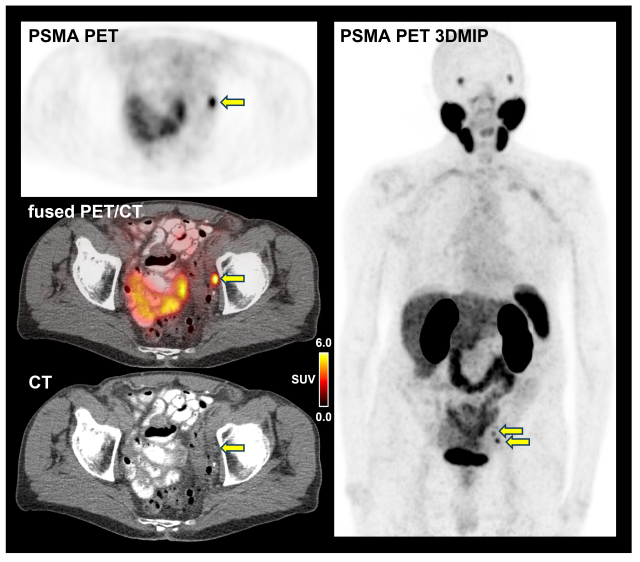

PSMA-PET/CT scan of an 85-year-old patient with hormone-sensitive prostate cancer.

PSMA-PET/CT images of an 85-year-old patient with hormone-sensitive prostate cancer. The whole-body PET image (see right) shows two areas of focally increased PSMA tracer uptake in the pelvis, suspicious for metastatic disease (see arrows). While CT images show unremarkable pelvic lymph nodes (see bottom left, lymph node size: 1.1 cm x 0.7 cm), intense focal tracer uptake on PSMA-PET (see top left, SUVmax 7.1) indicates the presence of lymph node metastases (see arrows). Figure provided by Dr. Adrien Holzgreve.